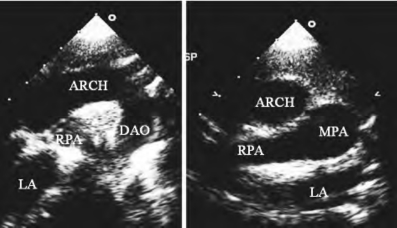

1.21.10第十节 大动脉转位

1.21.10.1一、完全型大动脉转位

1.21.10.2二、矫正型大动脉转位